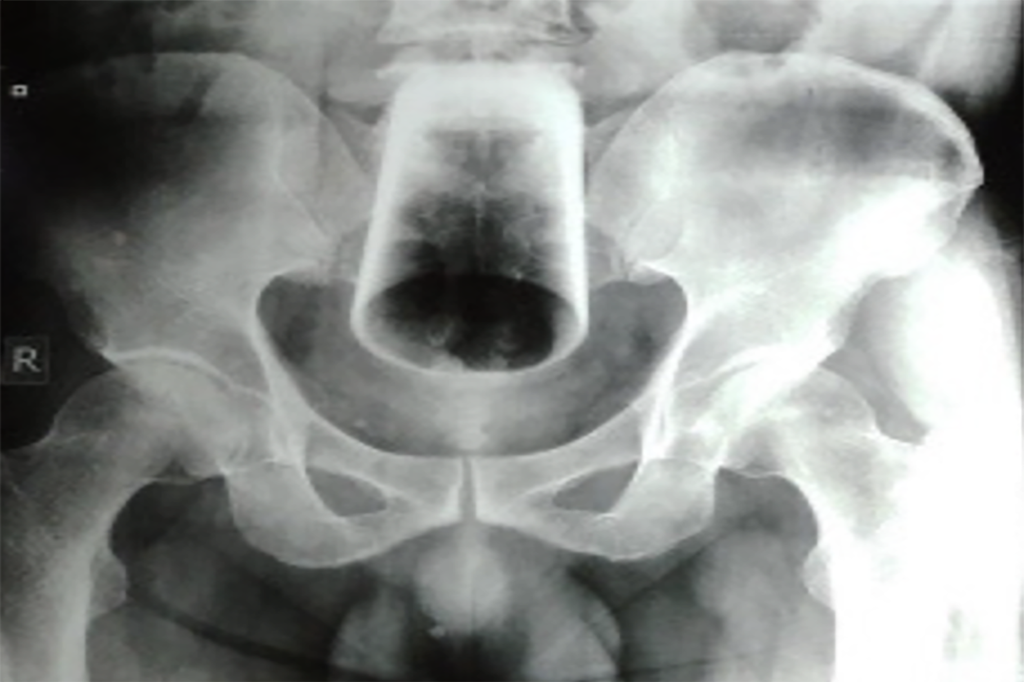

Bărbatul a spus că a încercat să scoată singur sticla, dar nu a reușit. După ce i-au făcut o radiografie, medicii au încercat să îndepărteze paharul fără operație, dar nu au reușit să-l extragă, deoarece era inversat.

Personalul medical a efectuat apoi o laparotomie exploratorie, care este o intervenție chirurgicală de deschidere a abdomenului.

Intervenția medicală extrem de neobișnuită a ajuns în Journal of Nepal Medical Association. „S-a încercat absorbirea paharului prin anus, dar acest lucru nu a reușit, deoarece paharul era sus, răsturnat și strâns încastrat”, au explicat medicii.

A fost nevoie de o intervenție și mai complicată: „De aceea s-a făcut enterostomia sigmoidă și s-a extras paharul de sticlă”.

O enterostomie este incizia chirurgicală într-un intestin, care au permis medicilor accesul direct la obiectul de sticlă.